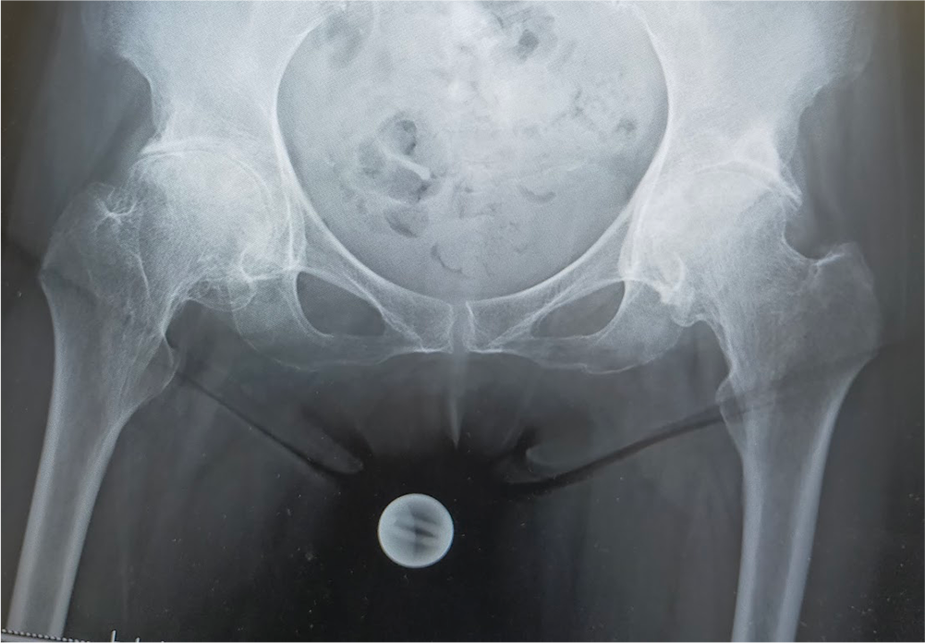

〈手術前のレントゲン〉